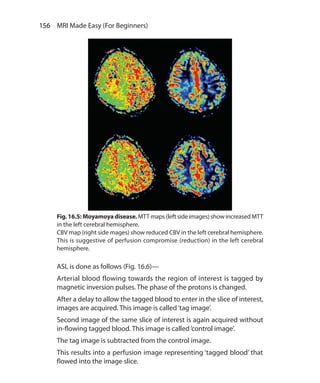

can be of short, medium or long TI.

ShortTI IR sequences useTI in the range of 80-150 ms and example

is STIR. In Medium TI IR sequences, TI ranges from 300 to 1200 ms, and

example is MPRAGE (Siemens). Long TI ranges from 1500 to 2500 ms

and example is FLAIR.

SHORT TI (tau) IR Sequence (STIR)